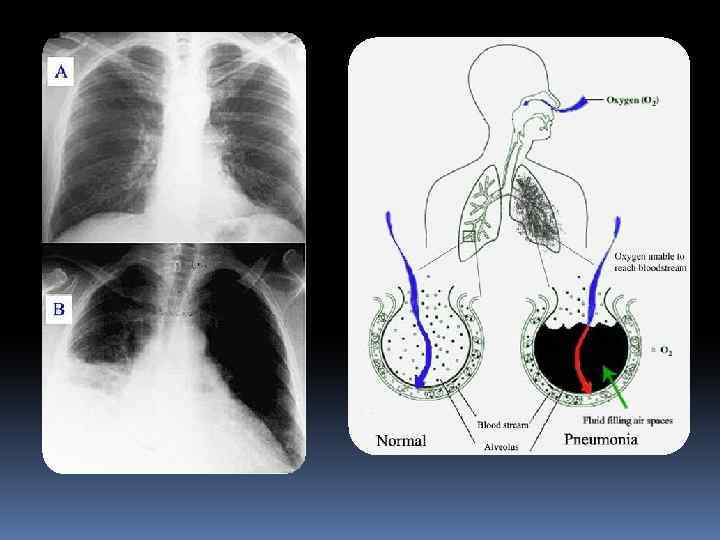

Пневмония— воспаление лёгочной ткани, как правило, инфекционного происхождения с преимущественным поражением альвеол (развитием в Пневмония— воспаление лёгочной ткани, как правило, инфекционного происхождения с преимущественным поражением альвеол (развитием в них воспалительной экссудации) и интерстициальной ткани лёгкого

Наиболее частым путём проникновения микроорганизмов в лёгочную ткань является бронхогенный — и этому способствуют: Наиболее частым путём проникновения микроорганизмов в лёгочную ткань является бронхогенный — и этому способствуют: аспирация, вдыхание микробов из окружающей среды, переселение патогенной флоры из верхних отделов дыхательной системы (нос, глотка) в нижний, медицинские манипуляции — бронхоскопия, интубация трахеи, искусственная вентиляция легких, ингаляция лекарственных веществ из обсеменённых ингаляторов и т. д. Гематогенный путь распространения инфекции (с током крови) встречается реже — при внутриутробном заражении, септических процессах и наркомании с внутривенным введением наркотиков. Лимфогенный путь проникновения встречается очень редко. Далее, при пневмонии любой этиологии, происходит фиксация и размножение инфекционного агента в эпителииреспираторных бронхиол — развивается острый бронхит или бронхиолит различного типа — от лёгкого катарального до некротического. Распространение микроорганизмов за пределы респираторных бронхиол вызывает воспаление лёгочной ткани — пневмонию.